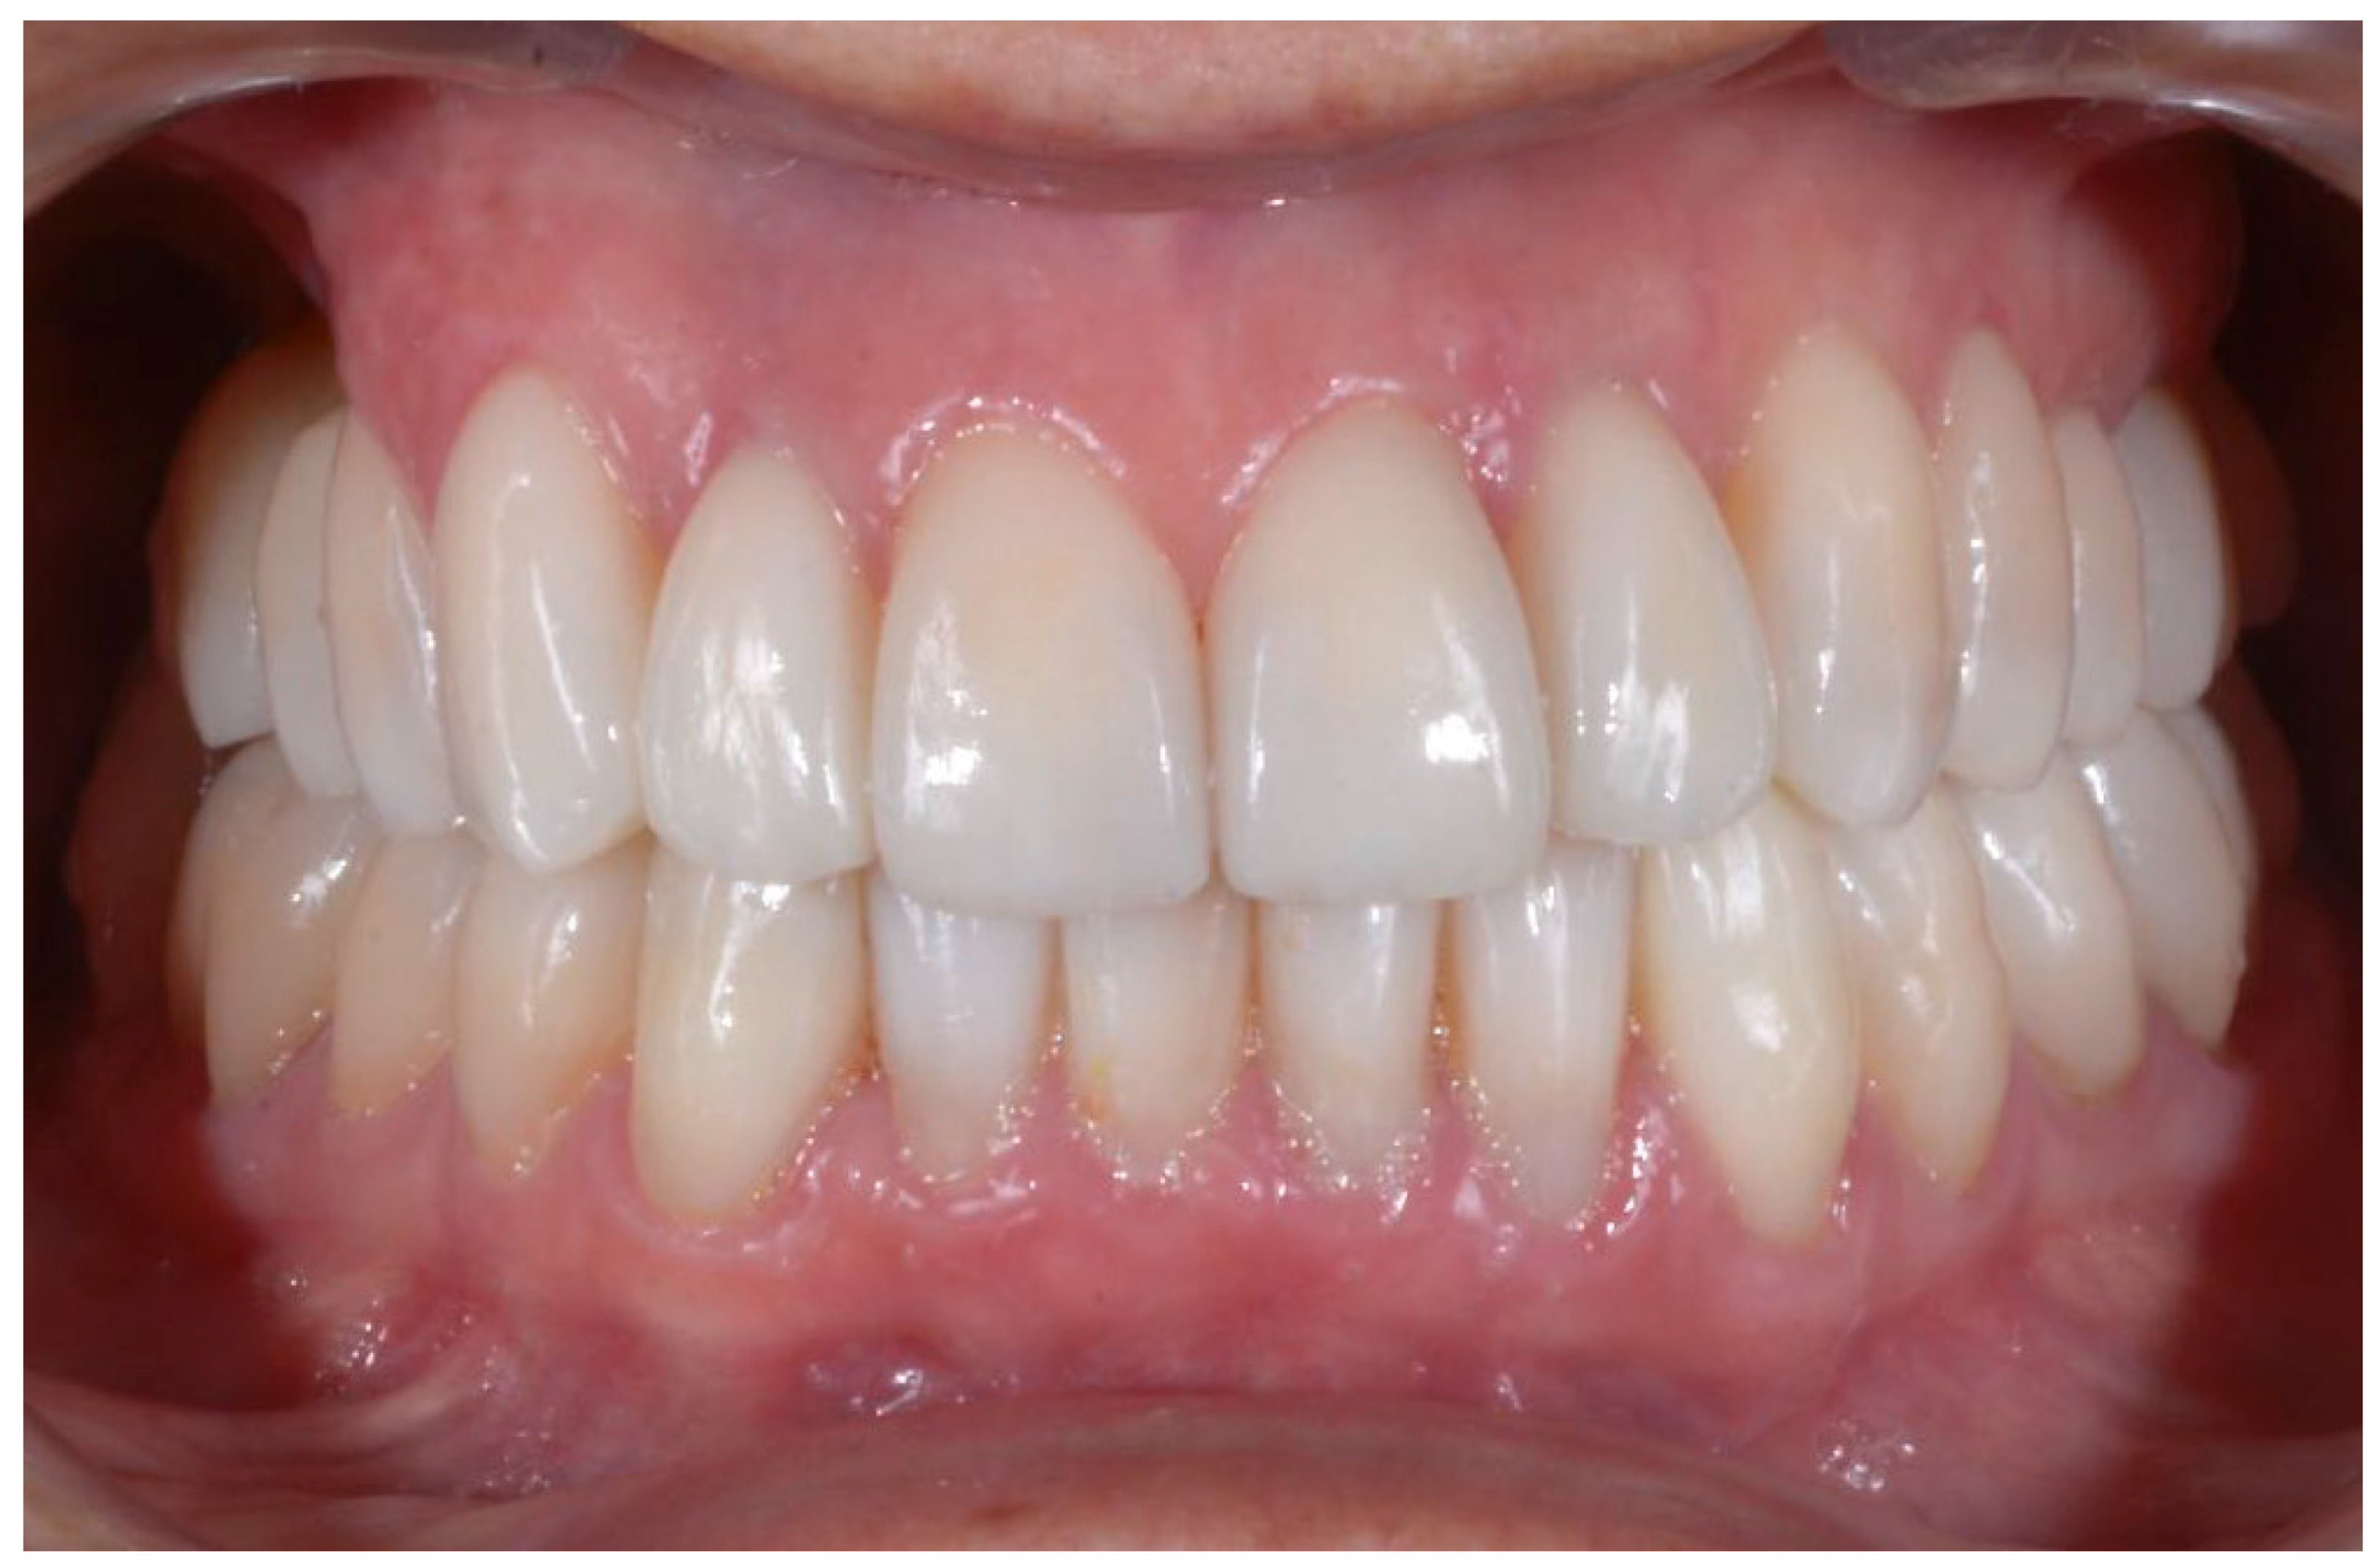

2.3. Outcome Achieved